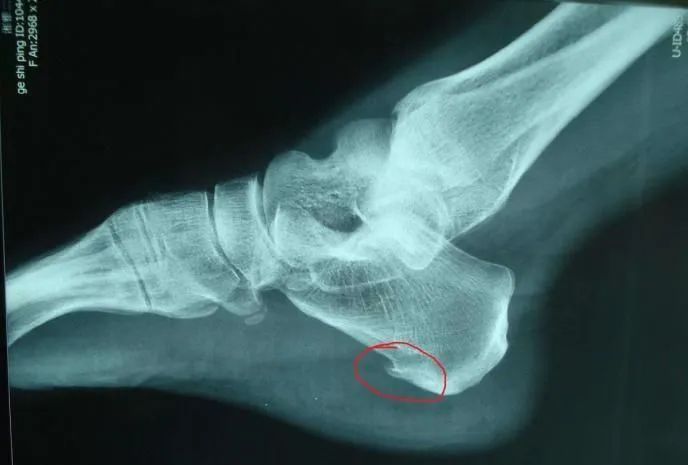

一、什么是足跟骨刺?

骨刺,是骨质增生的俗称。足跟骨刺即是足跟骨质增生,足跟骨刺是—种正常的生理退化现象,是人体的—种保护性生理反应,每个人都难以避免,区别仅仅是有的人出现得早些,有的出现得较晚些,—般在40岁以后。

五、跟骨骨刺的临床表现

足跟骨刺的症状表现与骨刺的大小、病发时间的长短、有无炎症等有关系。

1、脚后跟脚尖朝上脚后跟向下用力时,里面有针刺感觉,用手摸有麻痹的感觉;

2、长途步行引起劳累后疼痛又会加重,如走路时不慎踩在砖瓦块上 或下楼梯时,足部着地用力过猛,会引起剧烈疼痛;

3、足跟外表皮红肿,用手碰触发热;.

4、足跟中央有一个压痛点,用手指触压疼痛剧烈;

5、严重者无法踏地行走;

6、足根压痛,脚底疼痛,早晨重,下午轻,起床下地第一步痛不可忍,时轻时重,走路时脚跟不敢用,有石硌、针刺的感觉,活动开后症状减轻。